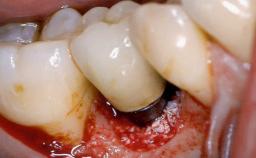

Open-Flap Debridement for the Management of Peri-Implant Mucositis Associated with Excess Cement

A 79-year-old female patient was referred to the Department of Periodontology of the University of Bern, Switzerland by her private dentist in May 2019. She had been rehabilitated in May 2005 with two tissue-level implants (Institut Straumann AG, Basel Switzerland) at sites 13 and 15, supporting a three-unit cemented fixed dental prosthesis (FDP). The metal-ceramic FDP had been cemented permanently with a glass-ionomer cement (Ketac Cem; 3M ESPE, Seefeld, Germany). Implant 13 had been diagnosed with peri-implant mucositis by the referring dentist in the course of regular supportive therapy. The patient was in good general health, did not smoke, and exhibited good self-performed plaque control.